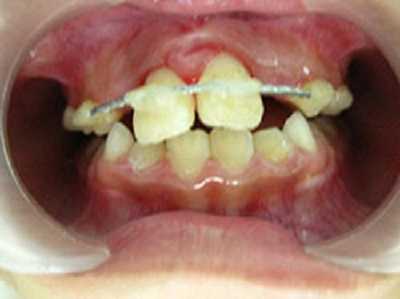

Bệnh nhi bị sưng đau 2 răng cửa giữa vĩnh viễn hàm trên, răng cửa hàm trên bên trái gần như sắp rớt ra ngoài vì chỉnh răng không đúng.

(VTC News) - Bệnh nhi bị sưng đau 2 răng cửa giữa vĩnh viễn hàm trên, răng cửa hàm trên bên trái gần như sắp rớt ra ngoài vì chỉnh răng không đúng.

Bé  bị sưng đau 2 răng cửa giữa vĩnh viễn hàm trên, 2 răng này lung lay nhiều theo chiều dọc và theo chiều ngang, nặng nhất là răng cửa hàm trên bên trái gần như sắp rớt ra ngoài.

Răng bé được nắn chỉnh lại.

Bé được chỉnh răng phục hồi lại.

Khám lâm sàng cho thấy: gai nướu răng cửa hàm trên sưng đỏ, 2 răng cửa hàm trên bên phải lung lay độ 3, răng cửa hàm trên bên trái lung lay độ 4, cả 2 răng này tụt nướu nhiều, lộ cổ răng 1.3 mm. Chụp phim Xquang thấy tiêu xương nhiều ở vùng cổ răng, răng cửa hàm trên bên trái trồi khỏi ổ răng 1/3 chiều dài chân răng.

Các bác sĩ đã tiến hành gây tê tại chỗ, sau nó nắn chỉnh đưa 2 răng cửa hàm trên về đúng vị trí ban đầu và cố định 2 răng này theo cung răng hàm trên. Sau 1 tuần, răng bé bớt lung lay nhiều và bé có thể ăn uống bình thường.

Sau 2 tuần, răng bé cứng chắc hoàn toàn, nướu răng hồng hào và hết sưng đỏ. Tuy nhiên, phần cổ răng vẫn còn bị lộ ra do dây chằng nha chu bị đứt không phục hồi được nên nhìn răng bé vẫn hơi dài so với bình thường.